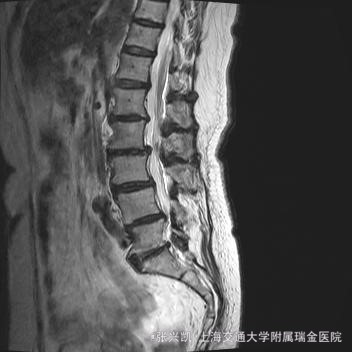

诊断: 腰椎侧弯,腰椎间盘突出 治疗:1期微创侧路椎体融合术+2期 微创后路经皮内固定术

患者侧路微创术后神经压迫症状减轻,腰椎矢状位及冠状位腰椎力线得到改善,戴支具术后可早期下床活动,术后2周后行后路固定手术。